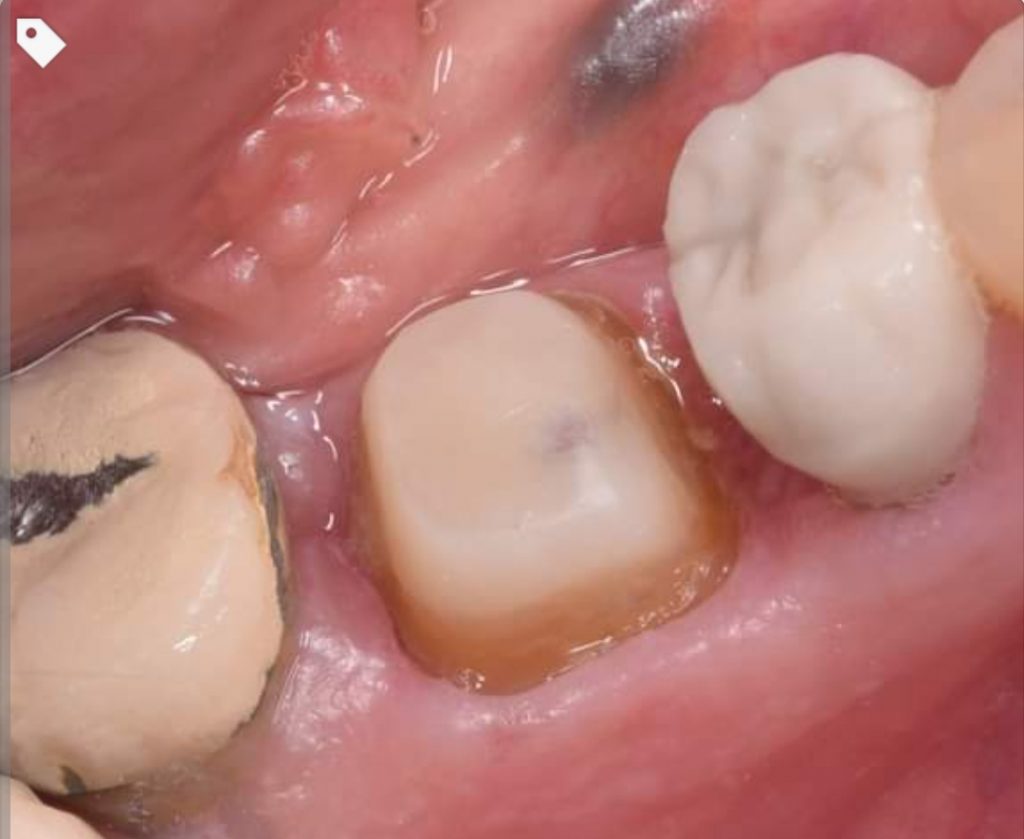

Saving lower first molar by removing the caries , gingivactomy and evaluation the restorability of the tooth